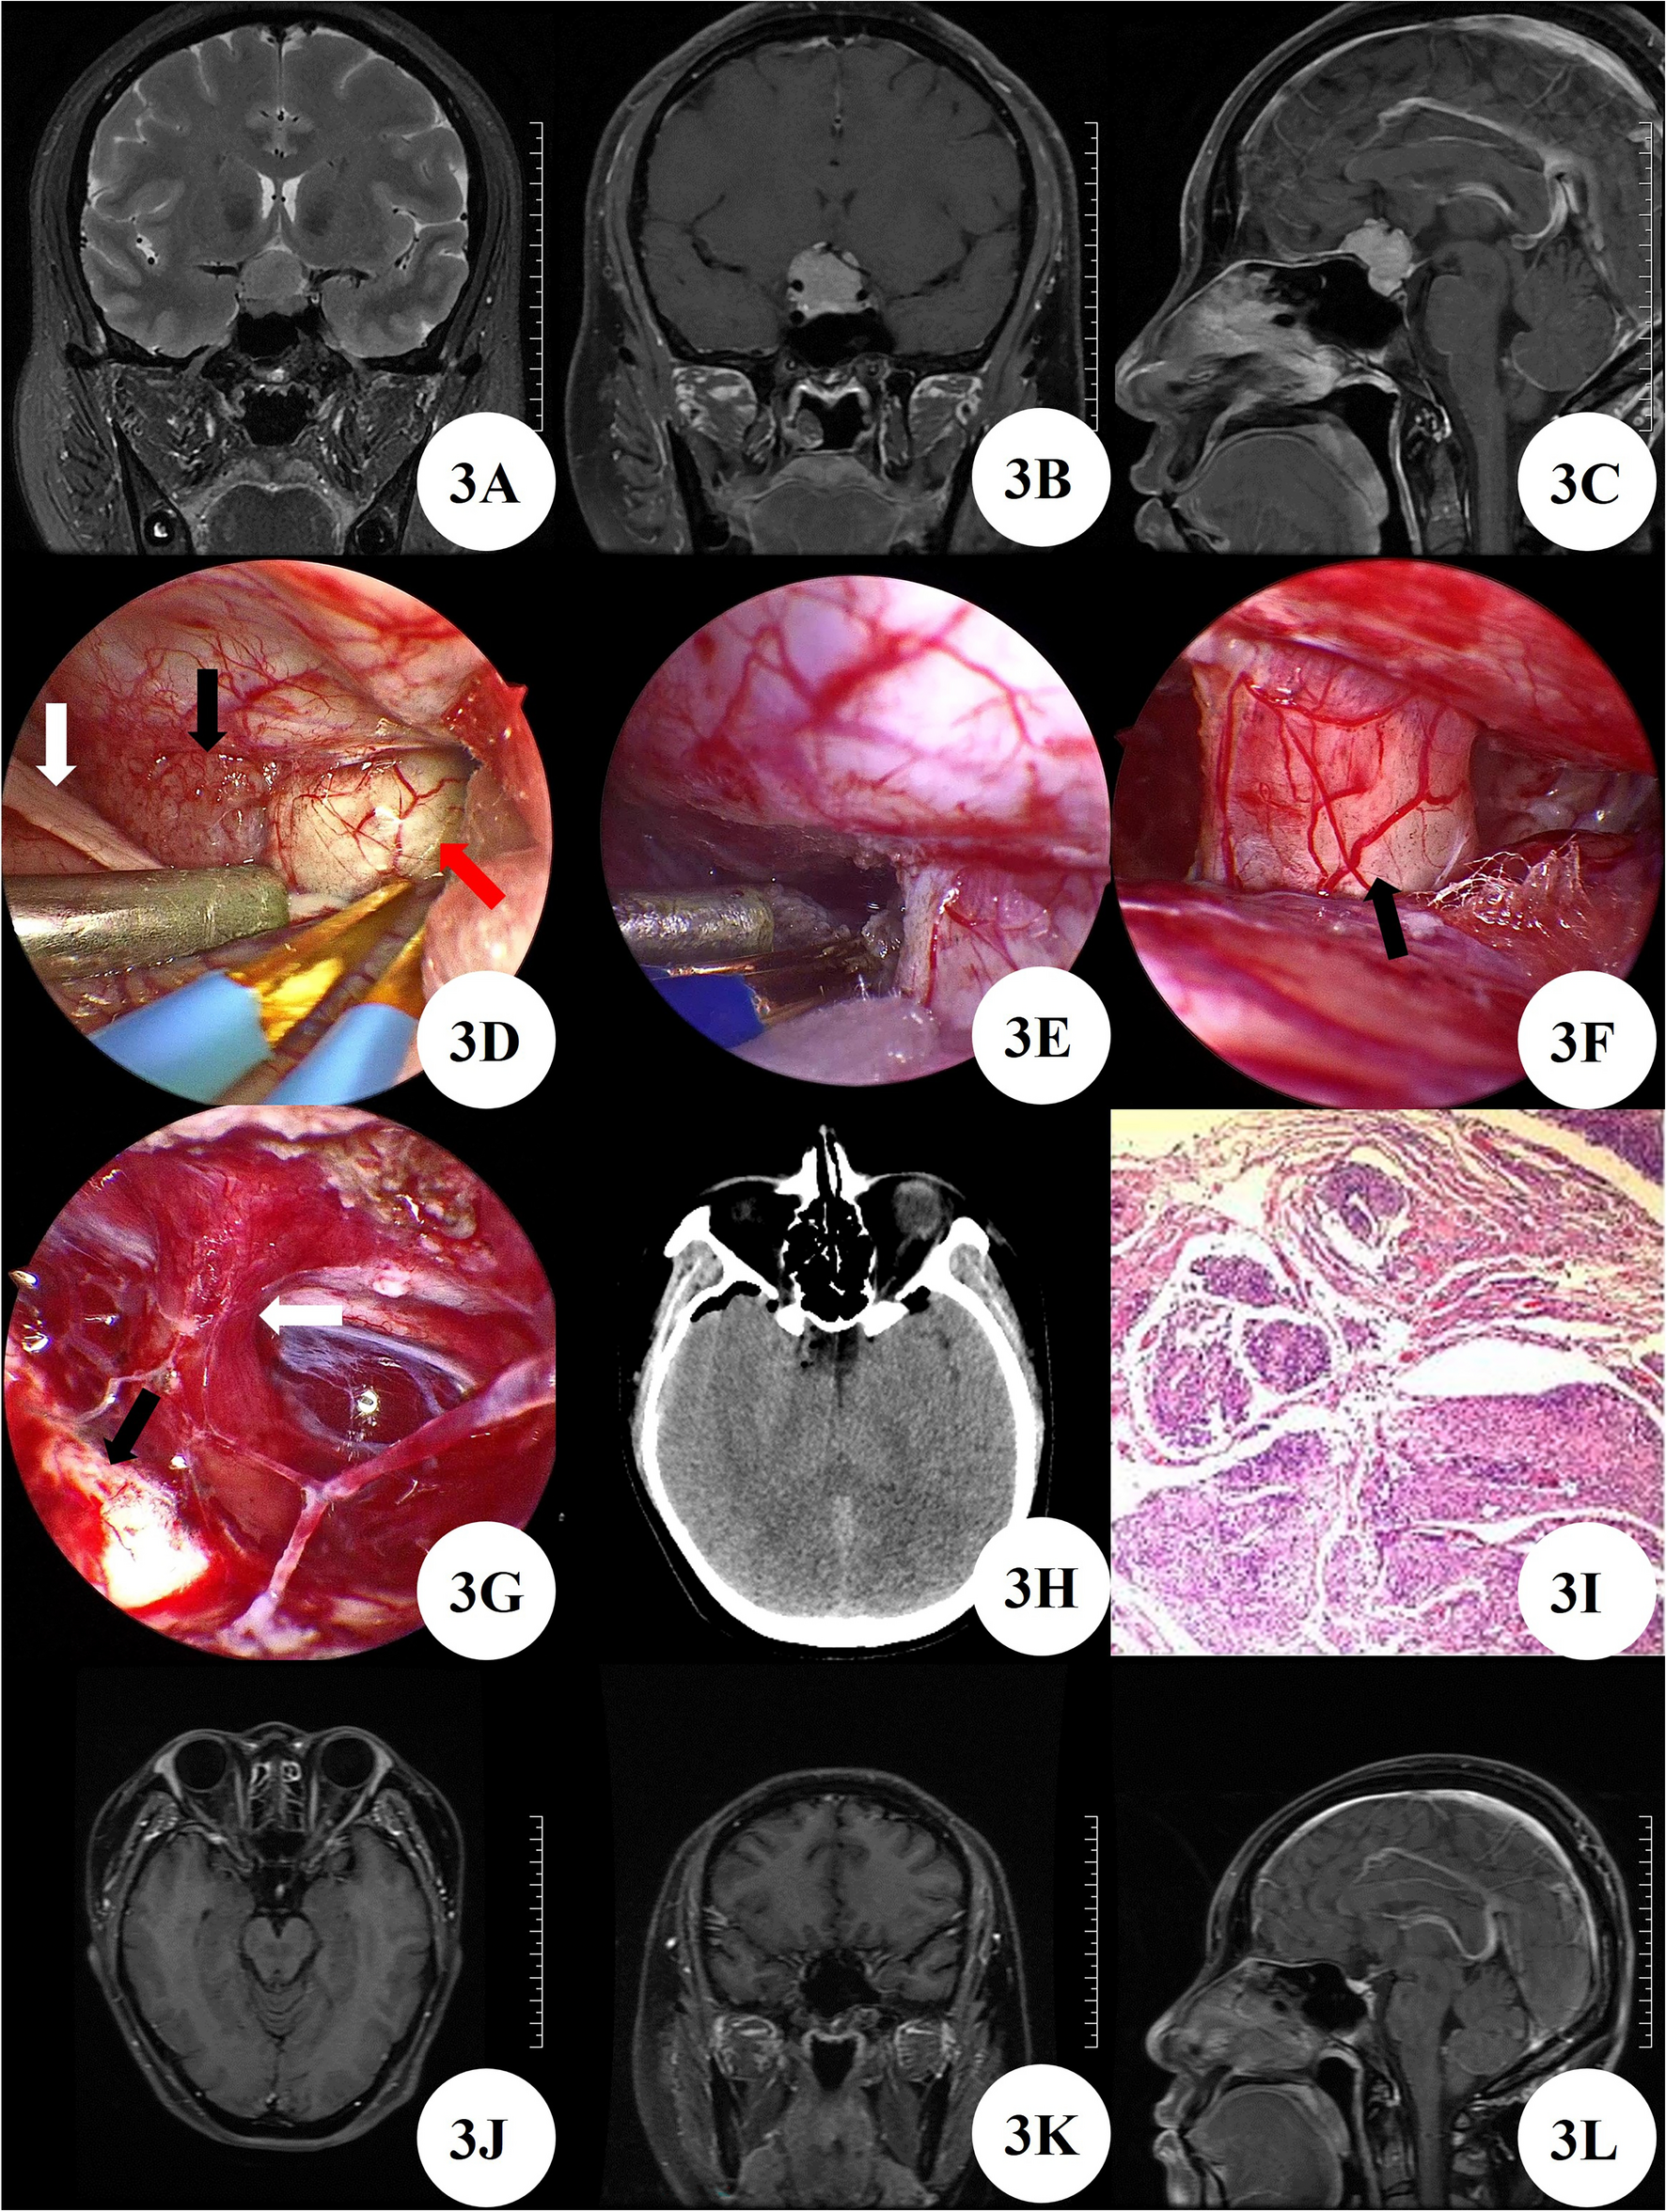

Figure 3

(A–C) Preoperative MRI shows mass lesions in the sellar region and suprasellar region. (D) Tumor (Black arrow), olfactory nerve (White arrow), and optic nerve visible (Red arrow) by neuroendoscopy. (E) Detachment of tumor base. (F) The right optic nerve is well preserved (Black arrow). (G) The pituitary stalk (White arrow) and left optic nerve (Black arrow) are well preserved. (H) Postoperative CT shows tumor resection with no bleeding in the surgical area. (I) Pathological examination diagnosed meningioma. (J–L) Follow up MRI at 8 months post-surgery showed no recurrence of the tumor.